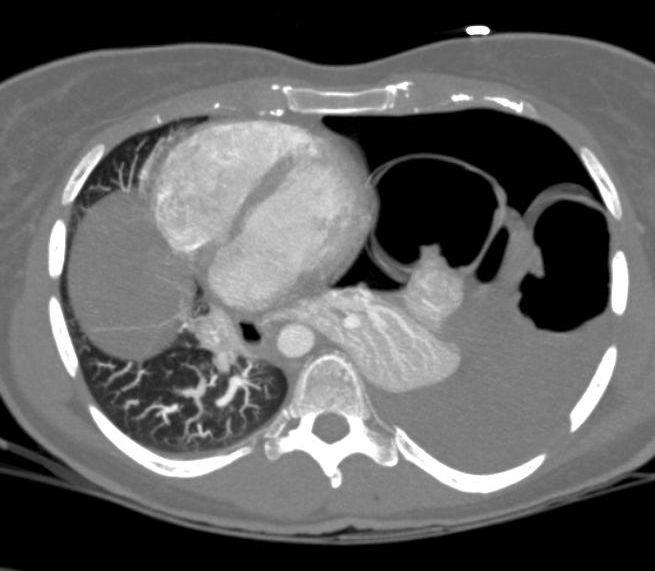

Multi-slice spiral CT-scan (Figure 2 [Fig. 2]) has a sensitivity as high as 80% with a specifity of 100%, according to various studies [11]. Moreover, when used as a diagnostic tool in patients with blunt or penetrating trauma or poly-traumatized patients it allows a fast and reliable scanning of all concomitant injuries. We observed a correct diagnosis by CT-scan in 10 of 12 patients (83%) with no false-positive results. Thus CT-scan is to date the study of choice to detect diaphragmatic injury.

Figure 2: Axial CT-scan of a patient with a right-sided diaphragmatic hernia. Tension-pneumothorax due to an intrathoracal gastric perforation.